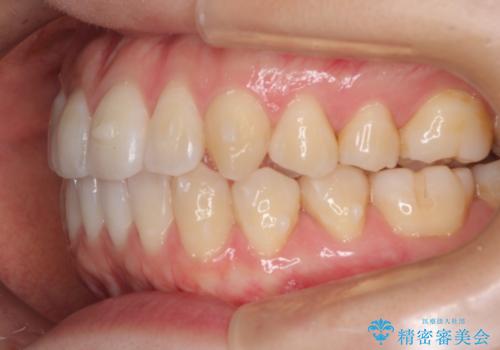

初診時の歯並びの状態としては、上下ともに前歯部に限局した軽度ののがたつき(叢生)がある状態でした。

主に歯列弓の拡大とディスキング(歯と歯の間に隙間を作る処置)を行い叢生を改善しました。